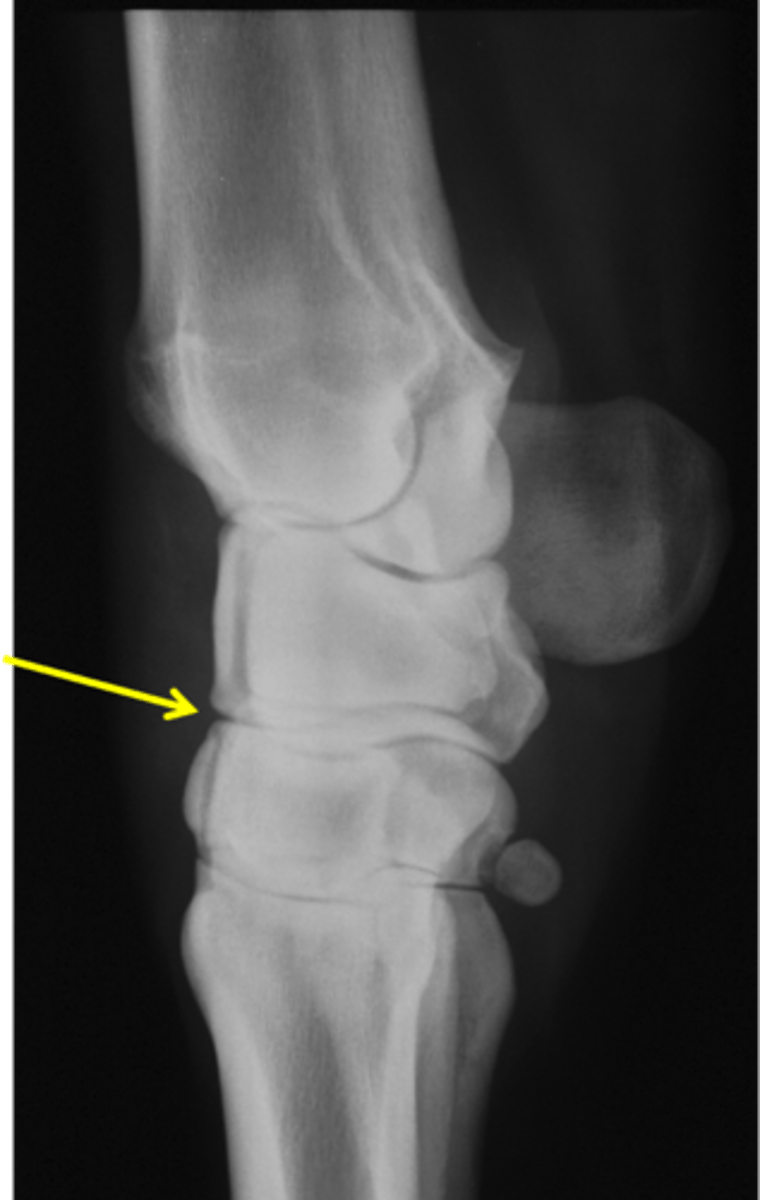

Pastern joint, LM

ID joint and view

Short pastern (P2)

Long pastern (P1)

Pastern joint (proximal interphalangeal joint)

Long pastern (P1)

Short pastern (P2)

Medullary cavity

Nutrient foramen of P2